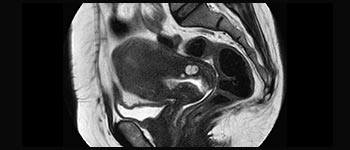

Frau Silvia Schiffer, leitende Radiologin bei Radiologie Schiffer in Deutschland, berichtet über ihre Erfahrungen mit dem Ingenia Prodiva 1.5T MR-System.